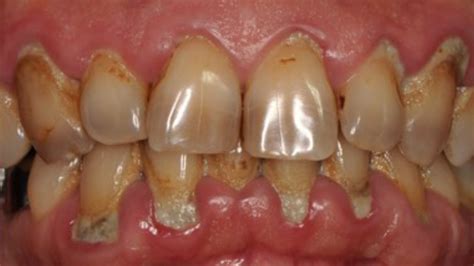

Advanced periodontal disease occurs when the bacteria in your mouth—which have already caused initial gingivitis and progressed into moderate periodontitis—begin to destroy the fibers and bone that anchor your teeth in place. As the infection deepens, the gums pull away from the teeth, creating "pockets" that become infected and difficult to clean. Over time, the body’s own inflammatory response to this infection begins to break down the surrounding bone and periodontal ligament, leading to loose teeth, shifting, and, eventually, tooth loss.

• Deep periodontal pockets: Pockets deeper than 5-6 mm are common, which are impossible to clean with regular brushing and flossing.

• Severely receding gums: Teeth may appear longer, or roots may become exposed.

• Pus between teeth and gums: An indicator of active, severe infection.